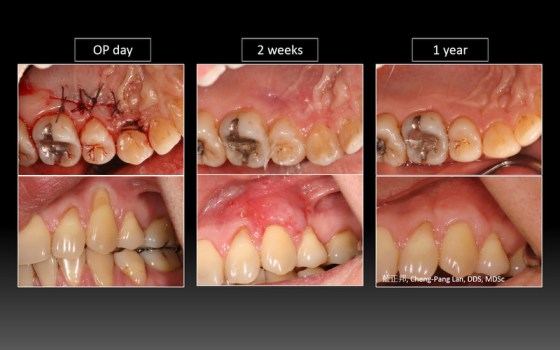

因為幫學會上課,藉由這次機會,整理了五個長期案例,至少八年到十二年的追蹤。觀察照片,移植角化上皮,經過長年觀察,粗略估計,一年後就很穩定,且多年後,萎縮量沒有很多,蠻平穩的。

以前台大老師有提過,時間久了,可能會因為肌肉層附連拉扯,即使補的寬度多很多,前後MGJ的連線還是會呈現一直線,原有多補的會縮一些回去。不過,我自己的案例,例如Case D,經過九年後,角化上皮還是很寬,呈現前後連線不是很一致的狀態。有這些發現,其實蠻有意思的~